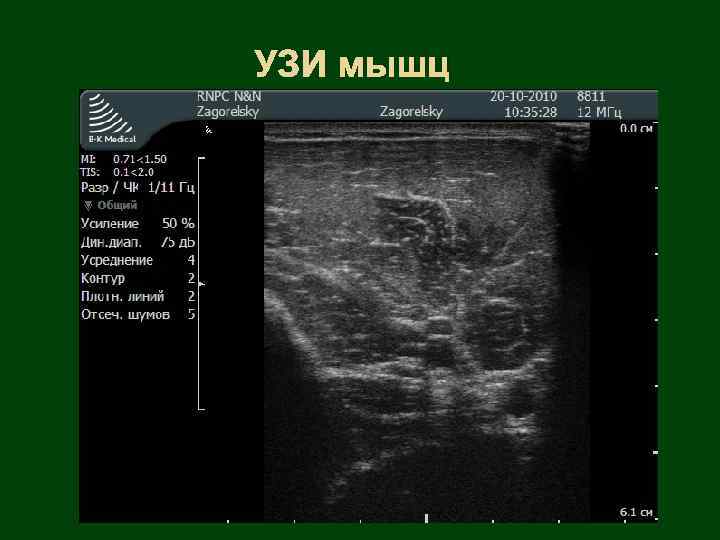

УЗИ мышц